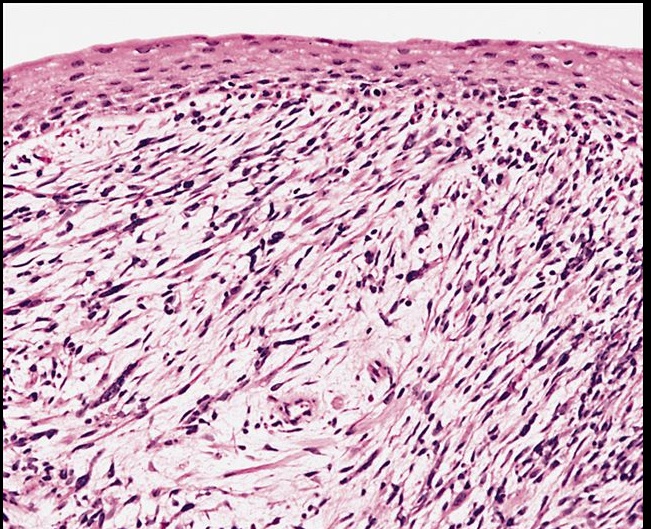

_Extramammary Paget Disease is characterized by malignant epithelial cells with pale cytoplasm and eccentric, hyperchromatic nuclei (Paget cells) in the epidermis of the vulva.

Extramammary disease, malignant paget cells infiltrating dermis. Epithelial near top. Looks like melanoma.

_Extramammary Paget disease represents carcinoma in situ (CIS), however, unlike paget disease of the nipple (breast involvement), there is usually no underlying carcinoma.

_It is very important to distinguish extramammary paget disease from melanoma, which is a lesion that rarely occurs on the vulva. The following histologic staining is used to make the differentiation:

Paget cells: PAS positive, keratin positive, S100 negative (Pas: mucous secretion from epithelial cells)

Melanoma: PAS negative, keratin negative, S100 positive